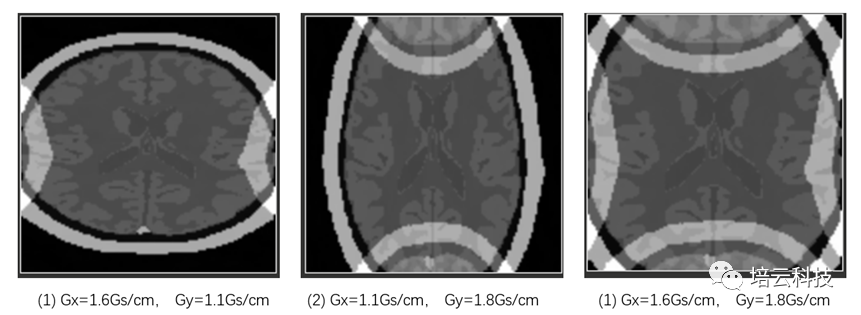

当采样带宽SW保持不变,分别调整三种梯度时:①Gx=1.6Gs/cm;②Gy=1.8Gs/cm;③Gx=1.6Gs/cm,Gy=1.8Gs/cm时,模拟采集得到的图像如图3所示,分别出现横向、纵向和横纵向的卷褶伪影。卷褶伪影出现的原因是,梯度过大,样品尺寸的左侧和右侧的自旋核产生的频率差,比决定视野范围的SW还要大时,超出的频率部分信号被卷褶到SW范围内了。根据频率和空间的映射关系,空间上也体现出图3所示的卷褶效果。

图3 不同的频率编码和相位编码梯度场下的卷褶伪影表现

仔细观察会发现,其卷褶是对侧进行的(图4所示),即左侧溢出的部分会卷褶到右侧,而右侧溢出的部分卷褶到左侧。同理,上下侧卷褶也是同样的。那么为什么必须是对侧卷褶的?很欣慰有好学的学子线上提出这个值得深究的问题。